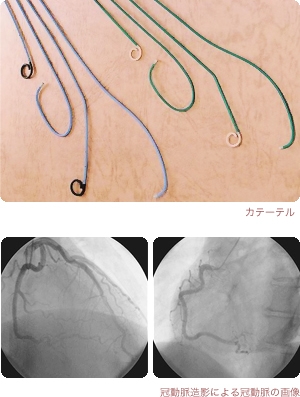

心臓カテーテル検査

手術ほどではないものの、身体への負担があり、時に危険性を伴う検査を侵襲的検査と言います。

心臓カテーテル検査は、心臓領域の侵襲的検査です。手首・太ももなどから血管に入れたカテーテルという細い管を、心臓まで進めてゆき、いろいろな検査をします。

検査の目的は、狭心症の重症度診断・治療方針の決定、心不全の原因検索・治療方針の決定、先天性心疾患や弁膜症などの手術の術前評価、冠動脈バイパス手術・心臓移植術などの術後評価などです。種々の心疾患の最終的診断は、この心臓カテーテル検査によってなされる場合が多いです。

入院せずに外来で検査する病院もありますが、安全性確保のため、当院では1泊か2泊の短期入院をお願いしています。検査は、手首か太ももを注射麻酔した後、動脈・静脈からカテーテルを心臓まで進めて、冠動脈の造影検査、左心室や大動脈の造影検査、心臓内圧や酸素濃度の計測、種々の薬物負荷テストなどのうち、患者さんの病状からみて必要な検査をします。検査は30-90分で終了しますが、終了後1-5時間はベッド上での安静が必要になります。

検査の危険性は、カテーテル操作とヨード造影剤によるものです。血管損傷による出血・血栓症、感染症、造影剤アレルギーなど、統計では0.05%-0.1%に致命的合併症が起こるとされています。必要性について十分な検討をした上で、施行すべき検査です。